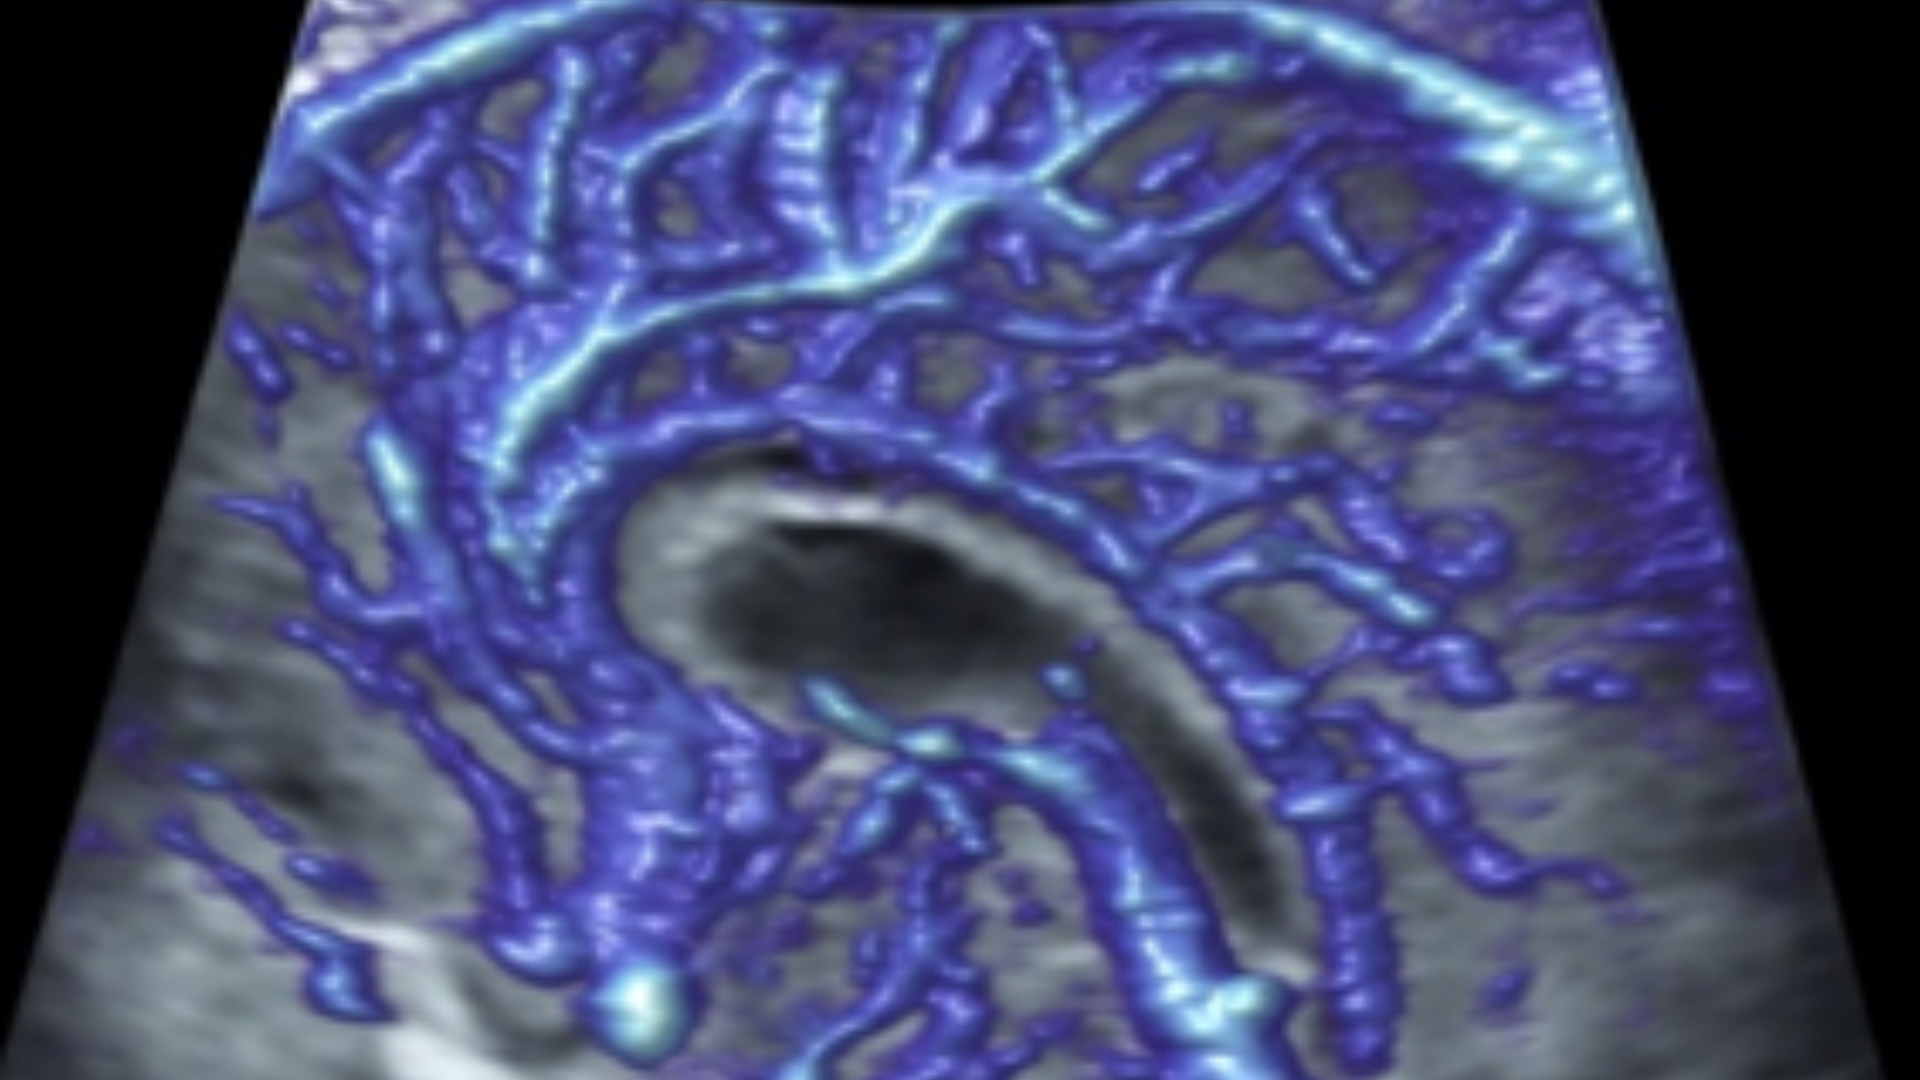

L’Université Paris Cité franchit une nouvelle étape dans le domaine de l’imagerie médicale anténatale avec l’acquisition d’un système d’Imagerie par Résonance Magnétique (IRM) 1,5T ARTIST™ de GE HealthCare. Cet équipement de pointe renforce les capacités de la Plateforme LUMIERE à l’hôpital Necker-Enfants malades, plateforme intégrée de soins, de recherche clinique et d’enseignement en imagerie médicale de la femme enceinte, du fœtus et du placenta.

L’acquisition de cette nouvelle IRM s’inscrit dans le cadre du protocole de recherche « LUMIERE SUR LE FETUS », dont les objectifs sont d’améliorer la prise en charge des pathologies anténatales, d’affiner leur pronostic et de contribuer à la réduction de la morbidité et de la mortalité à court, moyen et long terme. Cette acquisition a été rendue possible grâce au don exceptionnel de la Fondation LUMIERE d’un montant de 250k euros ainsi qu’au soutien de l’Université Paris Cité à hauteur de 670k euros.

Depuis 2020, la Plateforme LUMIERE offre aux femmes enceintes volontaires, entre 16 et 36 semaines d’aménorrhée et suivies à l’hôpital Necker-Enfants malades, la possibilité de participer activement à l’avancée de la recherche en médecine fœtale, tout en bénéficiant d’une IRM fœtale au cours de leur grossesse, réalisée dans un cadre sécurisé et encadré.

L’inclusion de ces patientes, depuis leur accueil jusqu’à la réalisation des examens d’imagerie, puis l’analyse des images et l’interprétation des résultats par des équipes expertes, enrichit une base de données structurée, unique au monde, au service de la recherche et de l’innovation en imagerie anténatale et en médecine fœtale.